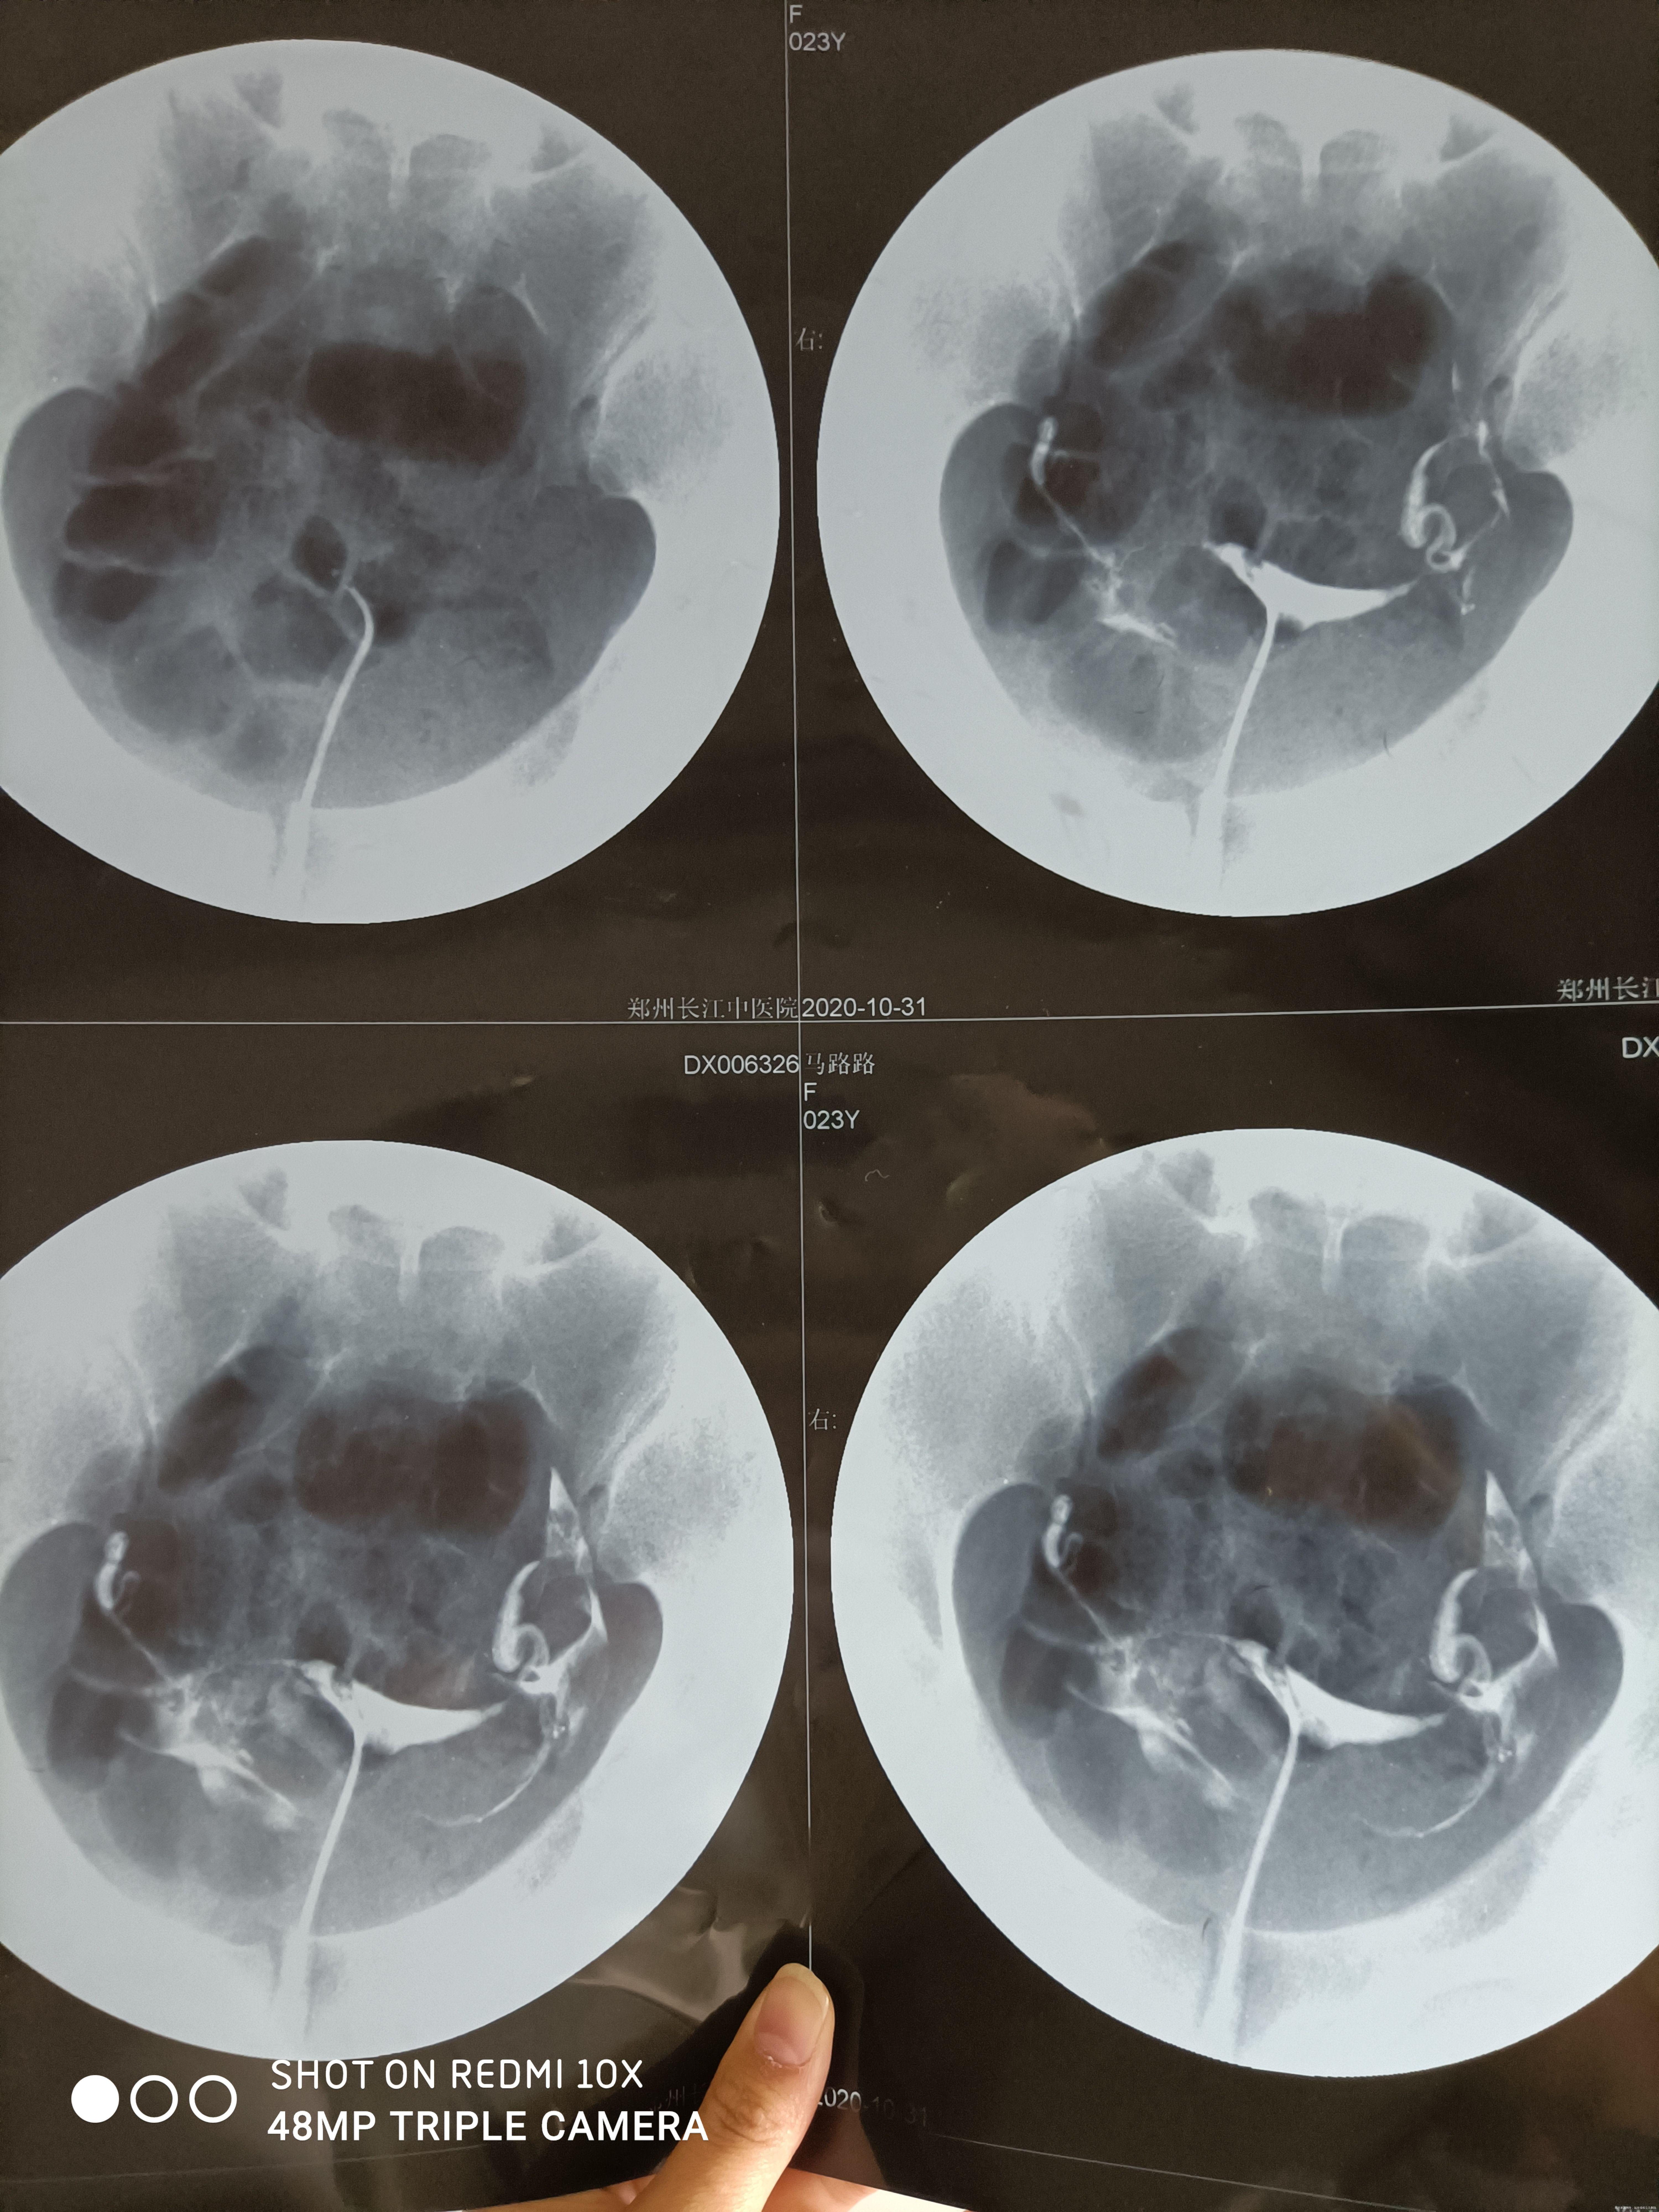

医生,您好。上个星期去一个小医院检查了,对结果不太清楚,想请您在帮忙看一下。医院说我性激六项正常,排卵监测一周正常,白带支原体阳性,慢性盆腔炎,输卵管造影伞端粘连并且堵塞。想问问到底我的造影显示,输卵管通不通,能不能怀孕。麻烦您了,谢谢!

你的输卵管是通的,但是有点不畅,激素6项也是对的,支原体阳性需要夫妻同治,治疗期间严格避孕避免交叉感染,可以选择输卵管通液后监测排卵或者促排卵。

有液体从伞端出来,只是伞端有点粘连流的就不畅,可以尝试通水把输卵管弄的更通畅些。

你好!你的输卵管通而不畅,有怀孕可能的。支原体感染,需要治愈后要孩子,可以做药物敏感实验,选择敏感抗生素,夫妻同治。排卵正常就好。盆腔炎,也需要治疗。男方精液常规查过吗?正常吗?治疗期间,最好做其他相关检查,综合评估生育力。

输卵管不通,盆腔炎及支原体阳性对怀孕都有影响。检查结果显示输卵管通而不畅,还是有怀孕可能的。建议及时治疗盆腔炎及支原体感染,同时保持心情舒畅,过于紧张压力过大或者是经常熬夜等因素也影响怀孕,祝早日好孕!